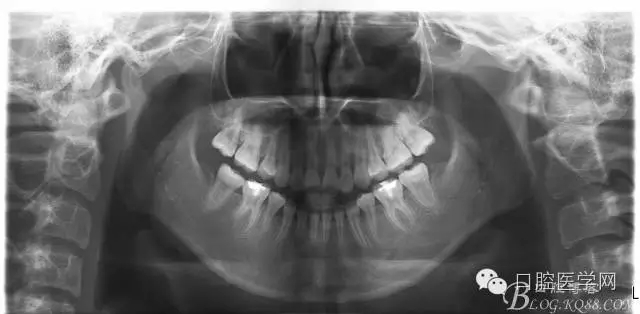

正畸查:替牙合。第一恒磨牙中性合。上牙弓尖圓型下牙弓方圓型。前牙覆合3度覆蓋7.5mm。下前牙咬到上舌側(cè)牙齦。上頜擁擠4.0mm,下頜擁擠

3.0mm。上頜稍前突下頜后縮,上下唇前突,上前牙覆蓋下唇,下唇外翻。面下三分之一過短,頦唇溝明顯,開唇露齒,頦饜窩明顯。顳下頜關(guān)節(jié)開閉口無彈響,無壓痛,開口型開口度正常。